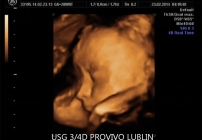

Badanie USG 3D/4D pozwala nie tylko na ocenę wybranych struktur i rozwoju ciąży, ale również na podgląd twarzy dziecka, jego ruchów oraz mimiki. To połączenie wartości diagnostycznej i wyjątkowego doświadczenia dla przyszłych rodziców.

Badanie USG 3D/4D w Lublinie umożliwia dokładny wgląd w rozwój płodu i pozwala zobaczyć dziecko w sposób zbliżony do jego aktualnego wyglądu. W porównaniu do klasycznego badania USG 2D obraz jest bardziej realistyczny i czytelny dla rodziców.

USG 3D daje możliwość trójwymiarowej rekonstrukcji obrazu płodu oraz wnętrza macicy. Dzięki temu można zobaczyć powierzchnię zewnętrzną ciała dziecka, a twarz płodu staje się znacznie wyraźniejsza niż w klasycznym badaniu 2D. To badanie szczególnie cenione przez rodziców, którzy chcą zobaczyć dziecko jeszcze przed porodem w bardziej realistyczny sposób. Na obecnej stronie PROVIVO wskazano również, że rodzice otrzymują zapis badania w formie elektronicznej.

USG 4D pokazuje obraz podobny do badania 3D, ale dodatkowo rejestruje go w czasie rzeczywistym. Oznacza to, że rodzice mogą obserwować ruchy dziecka, mimikę twarzy i zachowanie płodu niemal jak podczas podglądu na żywo.